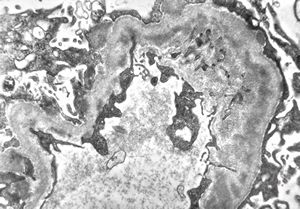

M,6y. | Alport syndrome- digital photo from the screen